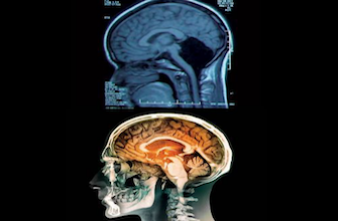

Dans cette histoire, cette jeune femme vit depuis sa naissance sans cervelet. Chez elle, l'emplacement habituel du cervelet est occupé par un fluide cérébral qui amortit le cerveau et constitue un moyen de défense immunitaire. Pour les médecins, son cas met en lumière la remarquable plasticité du cerveau.

Car le cervelet, appelé aussi « petit cerveau », représente 10 % du volume total du cerveau. Mais contient à lui seul 50 % des neurones », explique la journaliste de la revue scientifique Helen Thomson. De ce fait, il contrôle la motricité et l’équilibre. Sa défaillance peut donc conduire à une déficience mentale grave, à des troubles de motricité, provoquer des crises d’épilepsie, ou encore entraîner une accumulation mortelle de liquide dans le cerveau.